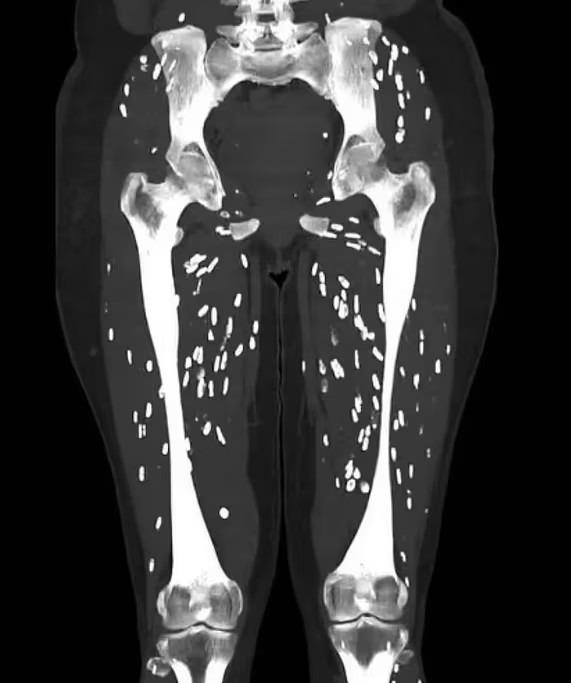

Tuy nhiên, xu hướng này vẫn gây ra mối lo ngại. Ngày 28/8, Tiến sĩ Sam Ghali, bác sĩ cấp cứu tại Đại học Florida Health Jacksonville (Mỹ), đăng một tấm ảnh đáng báo động.

Hình chụp CT cho thấy chân của một bệnh nhân chứa đầy nang sán, giống như hạt gạo, kéo dài từ xương đùi đến dưới đầu gối. Tiến sĩ Ghali cảnh báo: "Để tránh bệnh sán dây, bạn không bao giờ được ăn thịt lợn sống hoặc nấu chưa chín".

Chụp CT của một bệnh nhân được chẩn đoán mắc bệnh sán lợn. Ảnh: X